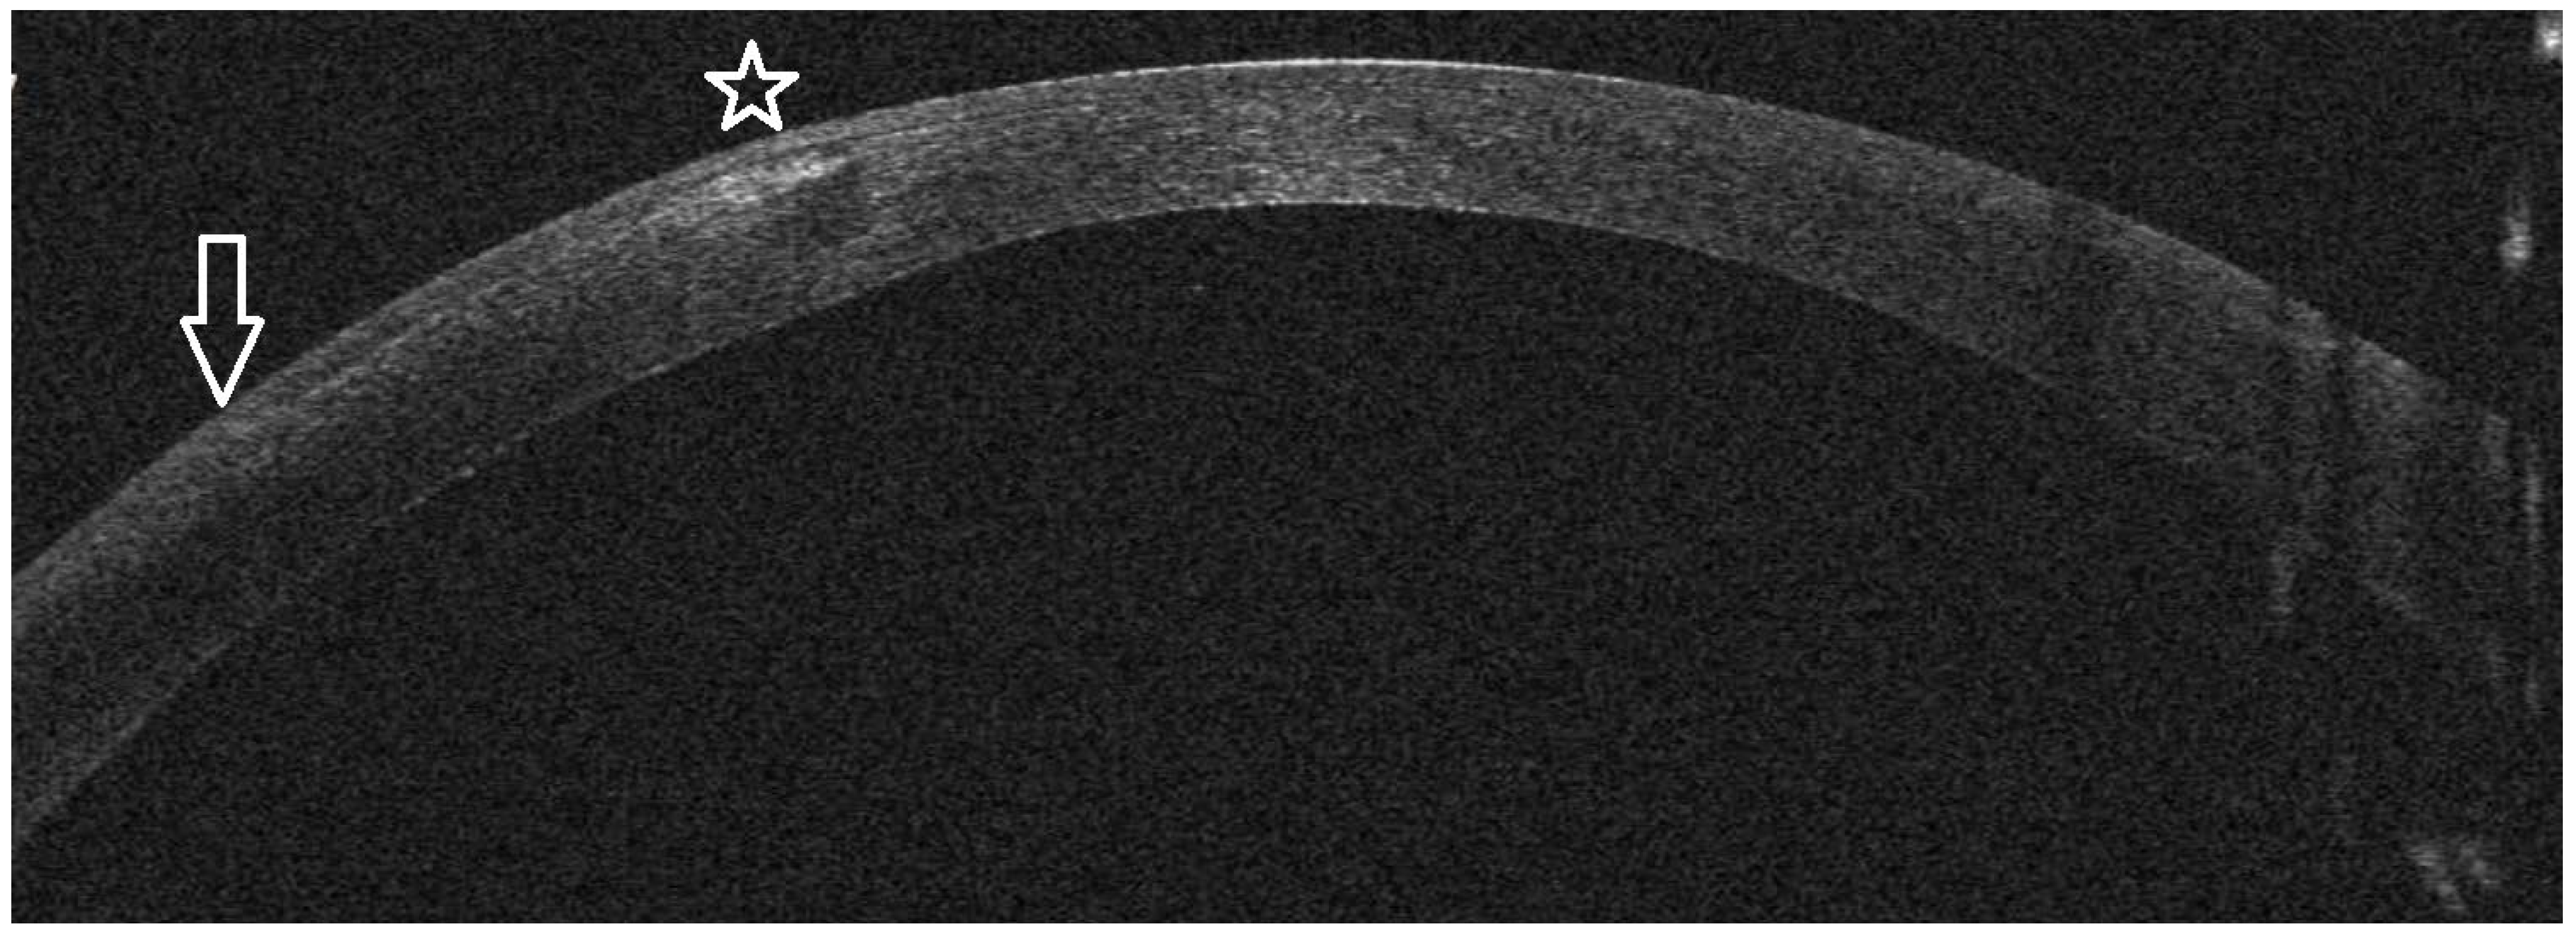

Infectious Keratitis Post-KLEx

AS-OCT Features